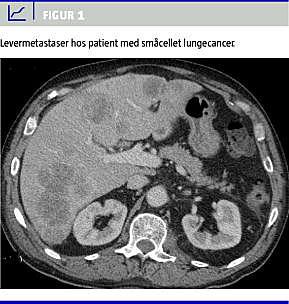

Supplerende blodprøver viste kraftigt forhøjet p-kortisol på 5.950 nmol/l (200-600 nmol/l) og p-adrenokortikotropt hormon (ACTH) på 619 ng/l (10-60 ng/l). Der forelå således svær hyperkortisolæmi betinget af forhøjet ACTH-produktion, og en CT (Figur 1 ) viste massiv progression i levermetastaserne. Der blev der opstartet andenlinjekemoterapi med topotecan, hvilket medførte en normalisering af p-kalium, et kraftigt fald i p-kortisol, p-ACTH og LDH og en bedring af patientens almentilstand.